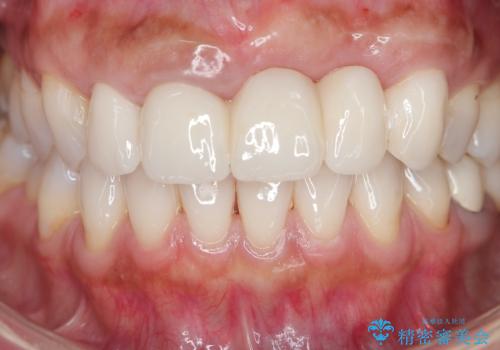

歯槽堤保存術を併用したブリッジ治療

抜歯時に可及的に歯肉のボリュームを保つよう骨充填材とコラーゲン製剤による填塞を行い審美的かつ機能的なブリッジとなるよう治療を進めます。

- 66万円(ジルコニアクラウン×5・仮歯×5)費用は治療当時の料金となります

一件綺麗に見えるセラミックも適合や精度が悪いと、内部で虫歯が進行し亀裂や破折、悪臭の原因となることがあります。